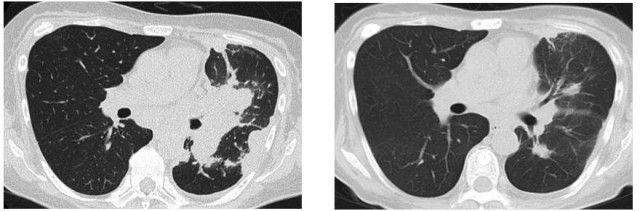

患者62岁,女性,2016年被确诊患有EGFR基因第19外显子缺失的IV期肺腺癌,在进行一段时间的吉非替尼治疗以后,患者病情得到缓解,2017年初,患者出现呼吸困难症状,经过再次活检发现T790M突变,随后开始印度卡布宁caprane奥希替尼治疗,治疗50天后,CT扫描结果发现患者右边结节收缩,右肺中叶和下肺叶斑片状毛玻璃样阴影减少。